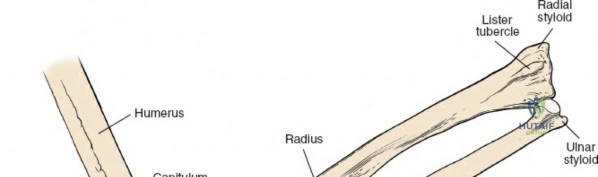

Osteology and Biomechanics of the Proximal Radius

The radius and ulna function together as a highly coordinated articular quadrangle. The proximal radius consists of the radial head, which articulates with the capitellum; the radial neck; and the bicipital tuberosity, which serves as the insertion site for the biceps brachii tendon. The biomechanics of the forearm dictate that the radius rotates around the stationary ulna during pronation and supination. The normal lateral curvature of the radius—the radial bow—is critical for this rotational clearance. Any surgical approach to the proximal radius must allow for the precise restoration of this bow, as even a minor malreduction can lead to profound deficits in forearm rotation.

Landmarks and Incision Planning

Accurate identification of surface landmarks is the first step in a successful Henry approach. Palpate the biceps tendon, a stout, taut structure crossing the anterior elbow joint just medial to the brachioradialis muscle. Next, palpate the brachioradialis itself, the fleshy muscle forming the lateral border of the cubital fossa. Finally, identify the styloid process of the radius distally. Note that when the forearm is fully supinated (the anatomic position), the radial styloid is truly lateral.

Make a straight or gently curved incision beginning at the anterior flexor crease of the elbow, just lateral to the biceps tendon. Extend this incision distally toward the styloid process of the radius. The exact length and placement of the incision are dictated by the specific pathology; the approach is highly modular, and often only the proximal, middle, or distal third of the incision is required.